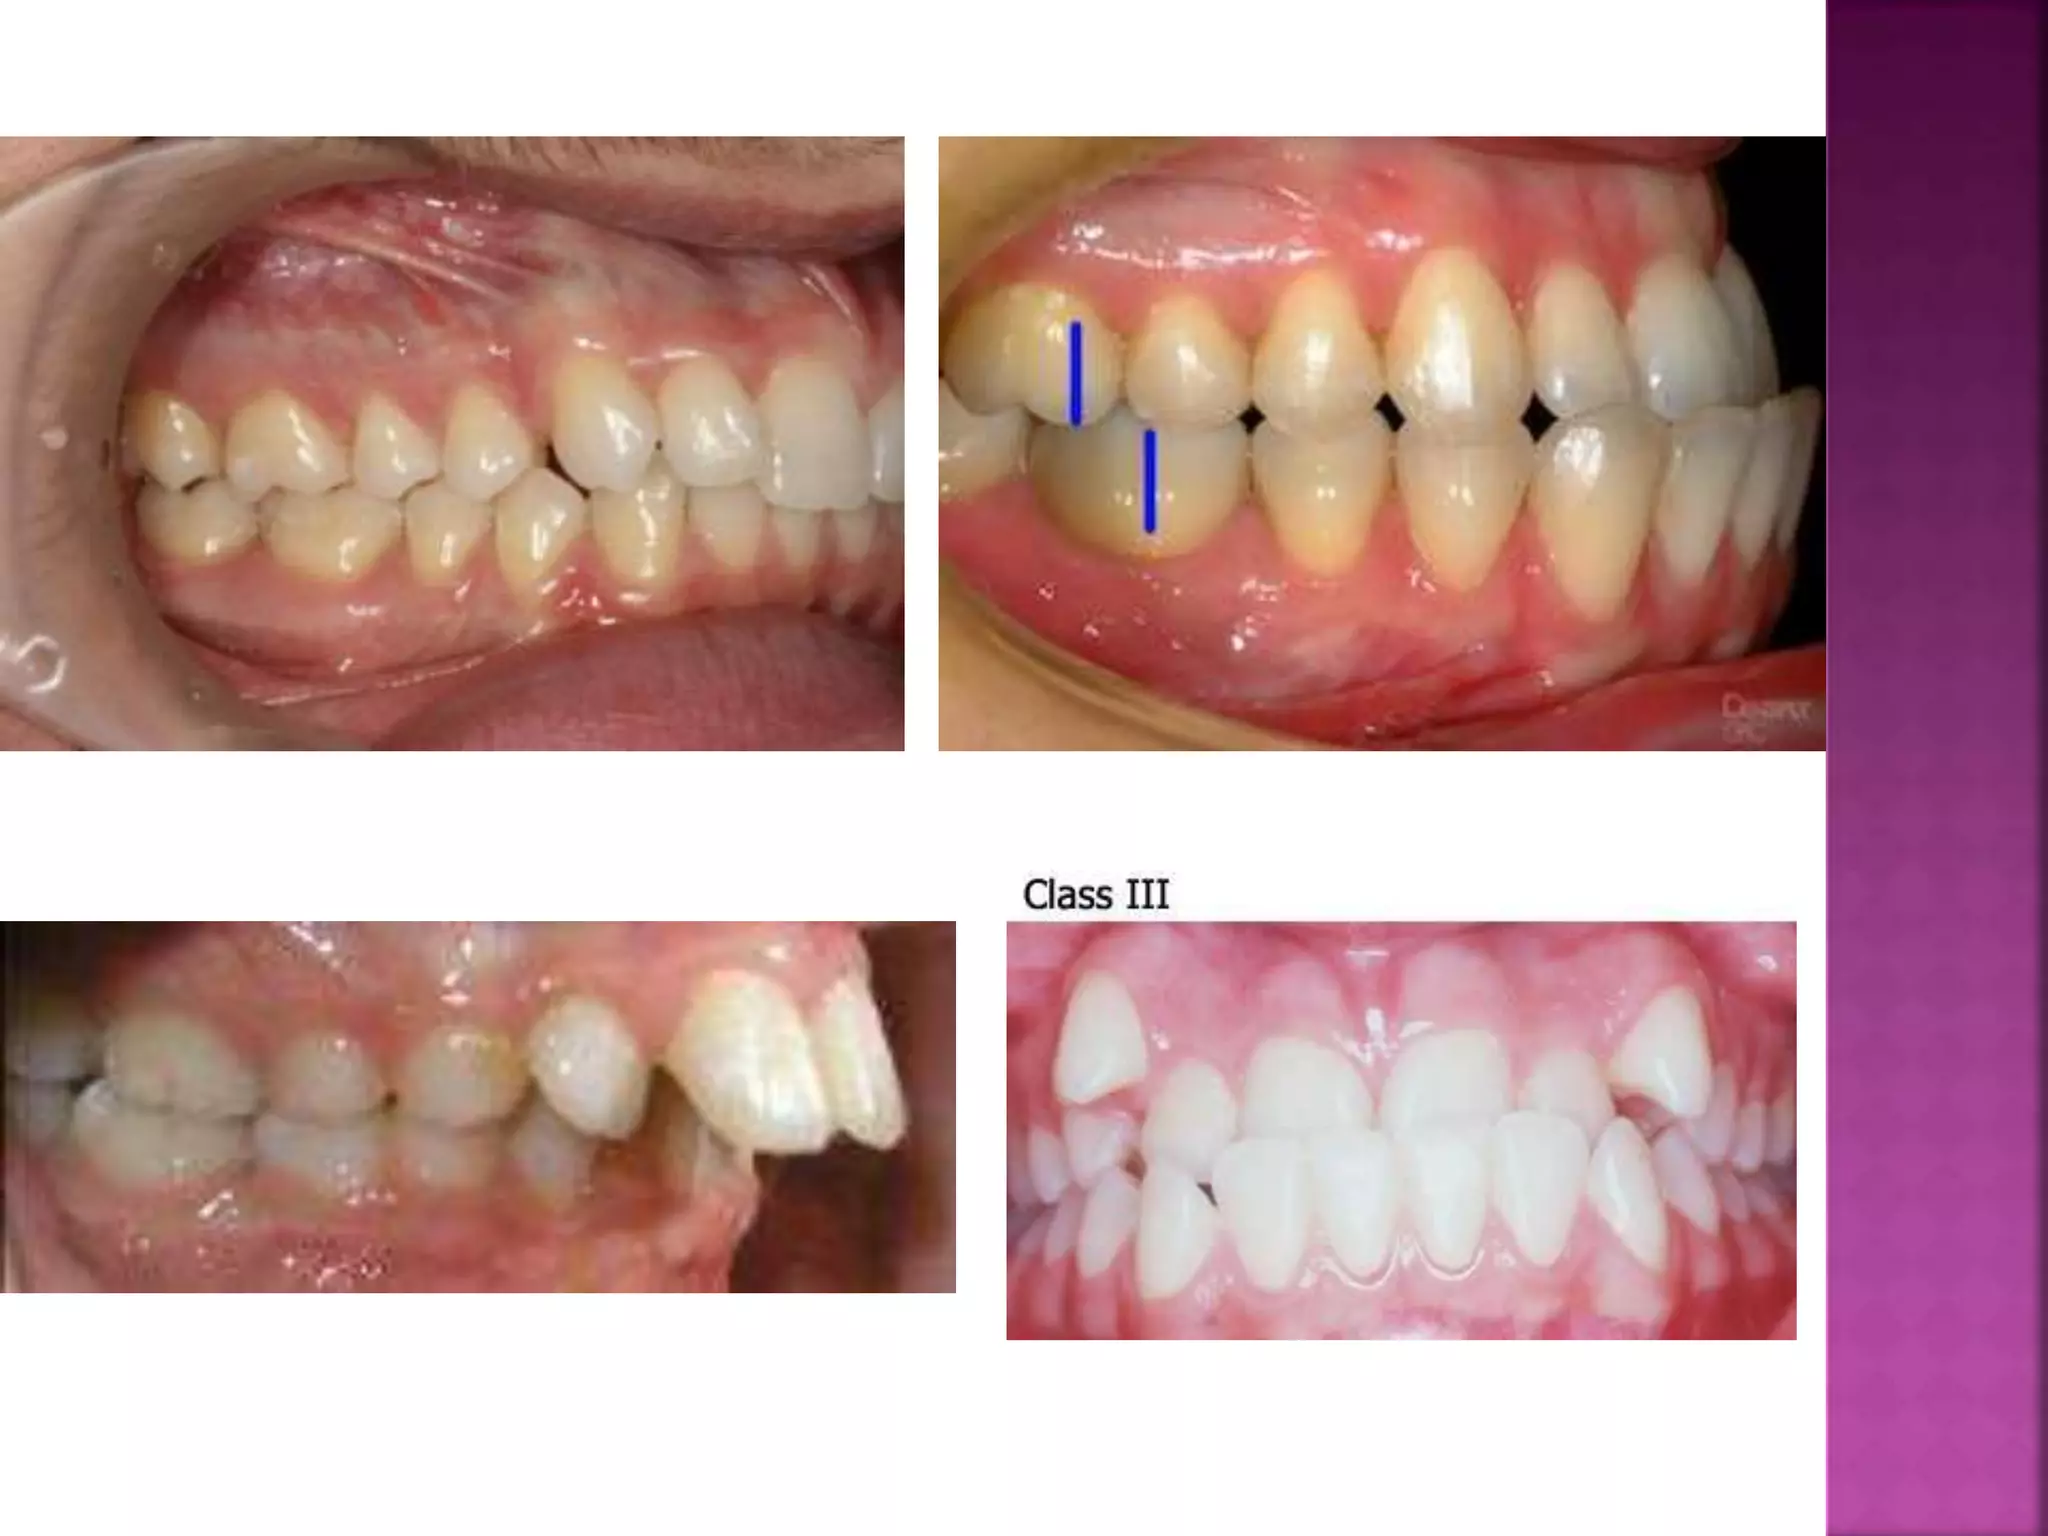

The position of each tooth within the jaw

is maintained by certain factors known as

the forces of occlusion . Normally there is

a balance of these forces which produce a

harmonious relationship of the teeth to

each other.

Any imbalance of these forces must affect

the normal relation of the teeth and / or

arches.

I- Growth;

Normal downward and forward growth of the face, by

harmonizing the size and form of title jaw with the

teeth may profoundly affect the position of the teeth.

Not only should the size of each jaw be adequate but

their relation should be correct.